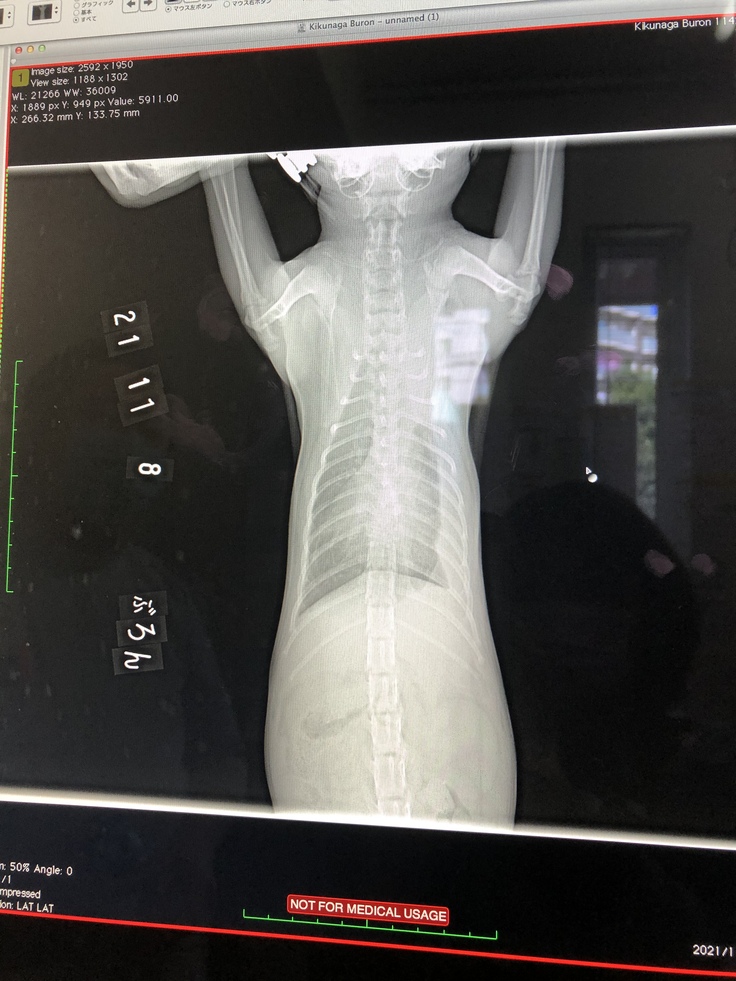

肺のレントゲン

レントゲン検査

体重 1.7kg 投薬量200mg

左肺が黒い部分が増え酸素が取り込めるようになったので、無気肺の危険性はないとの診断でした。心音も聞こえるようになっていました。いつ無気肺になってもおかしくないといわれていたので、少し安心しました。

左肺もさらに黒い部分が増え酸素が入ってきています。

左肺の胸水も減ってきて、黒い部分がかなり広がってきました。